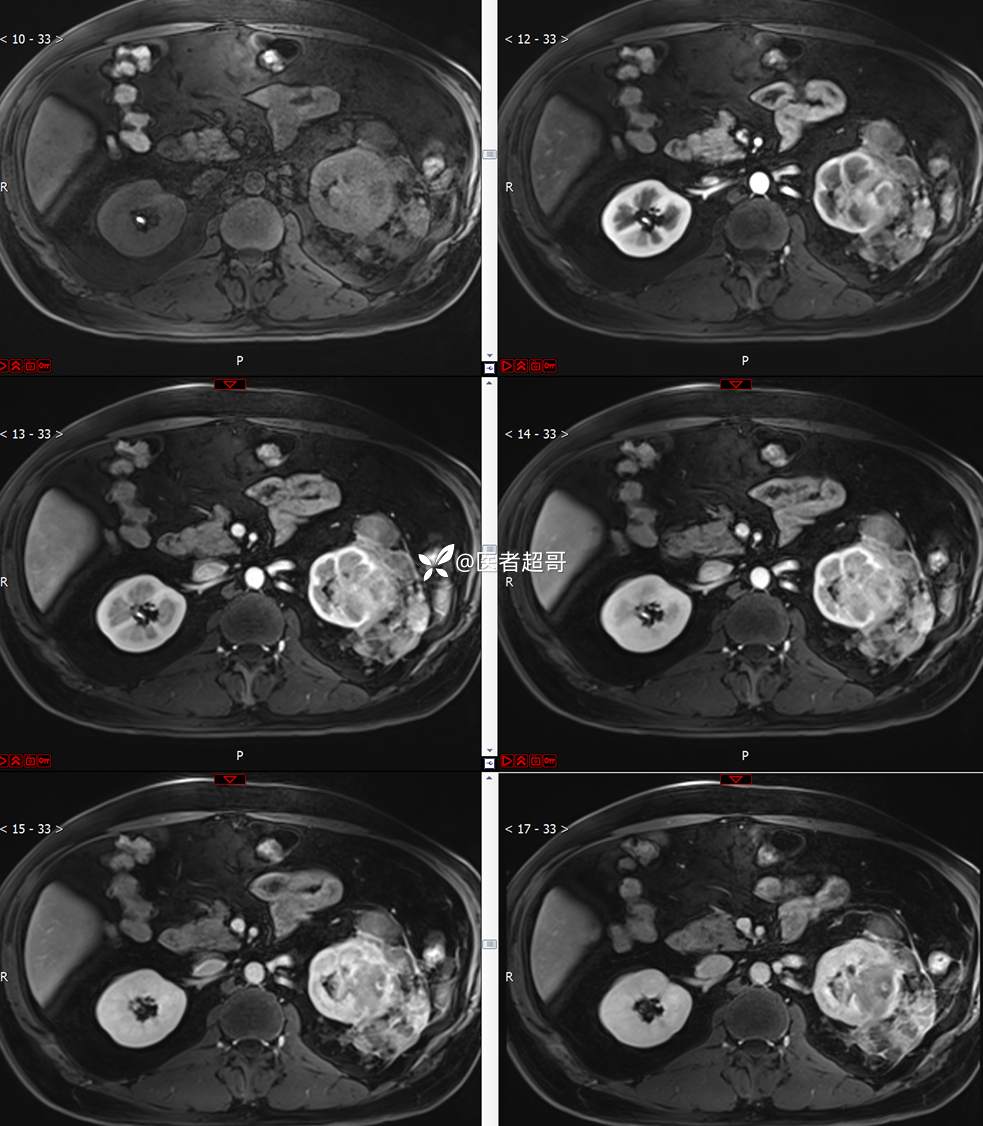

主 诉:查体发现左肾肿物9天。

现病史:患者9天前于附属医院行常规腹部CT检查时,发现左肾占位性病变并肾周脂间隙软组织增多,自述无明显腰腹部不适,无尿频、尿急、尿痛及肉眼血尿,未予特殊治疗,患者近期无头晕头迷,胸闷气急,腹胀腹泻及其他部位明显不适,遂至我院就诊,门诊以“肾肿物”收入院,患者自发病以来,精神可,睡眠饮食可,大便正常,体重无明显减轻。